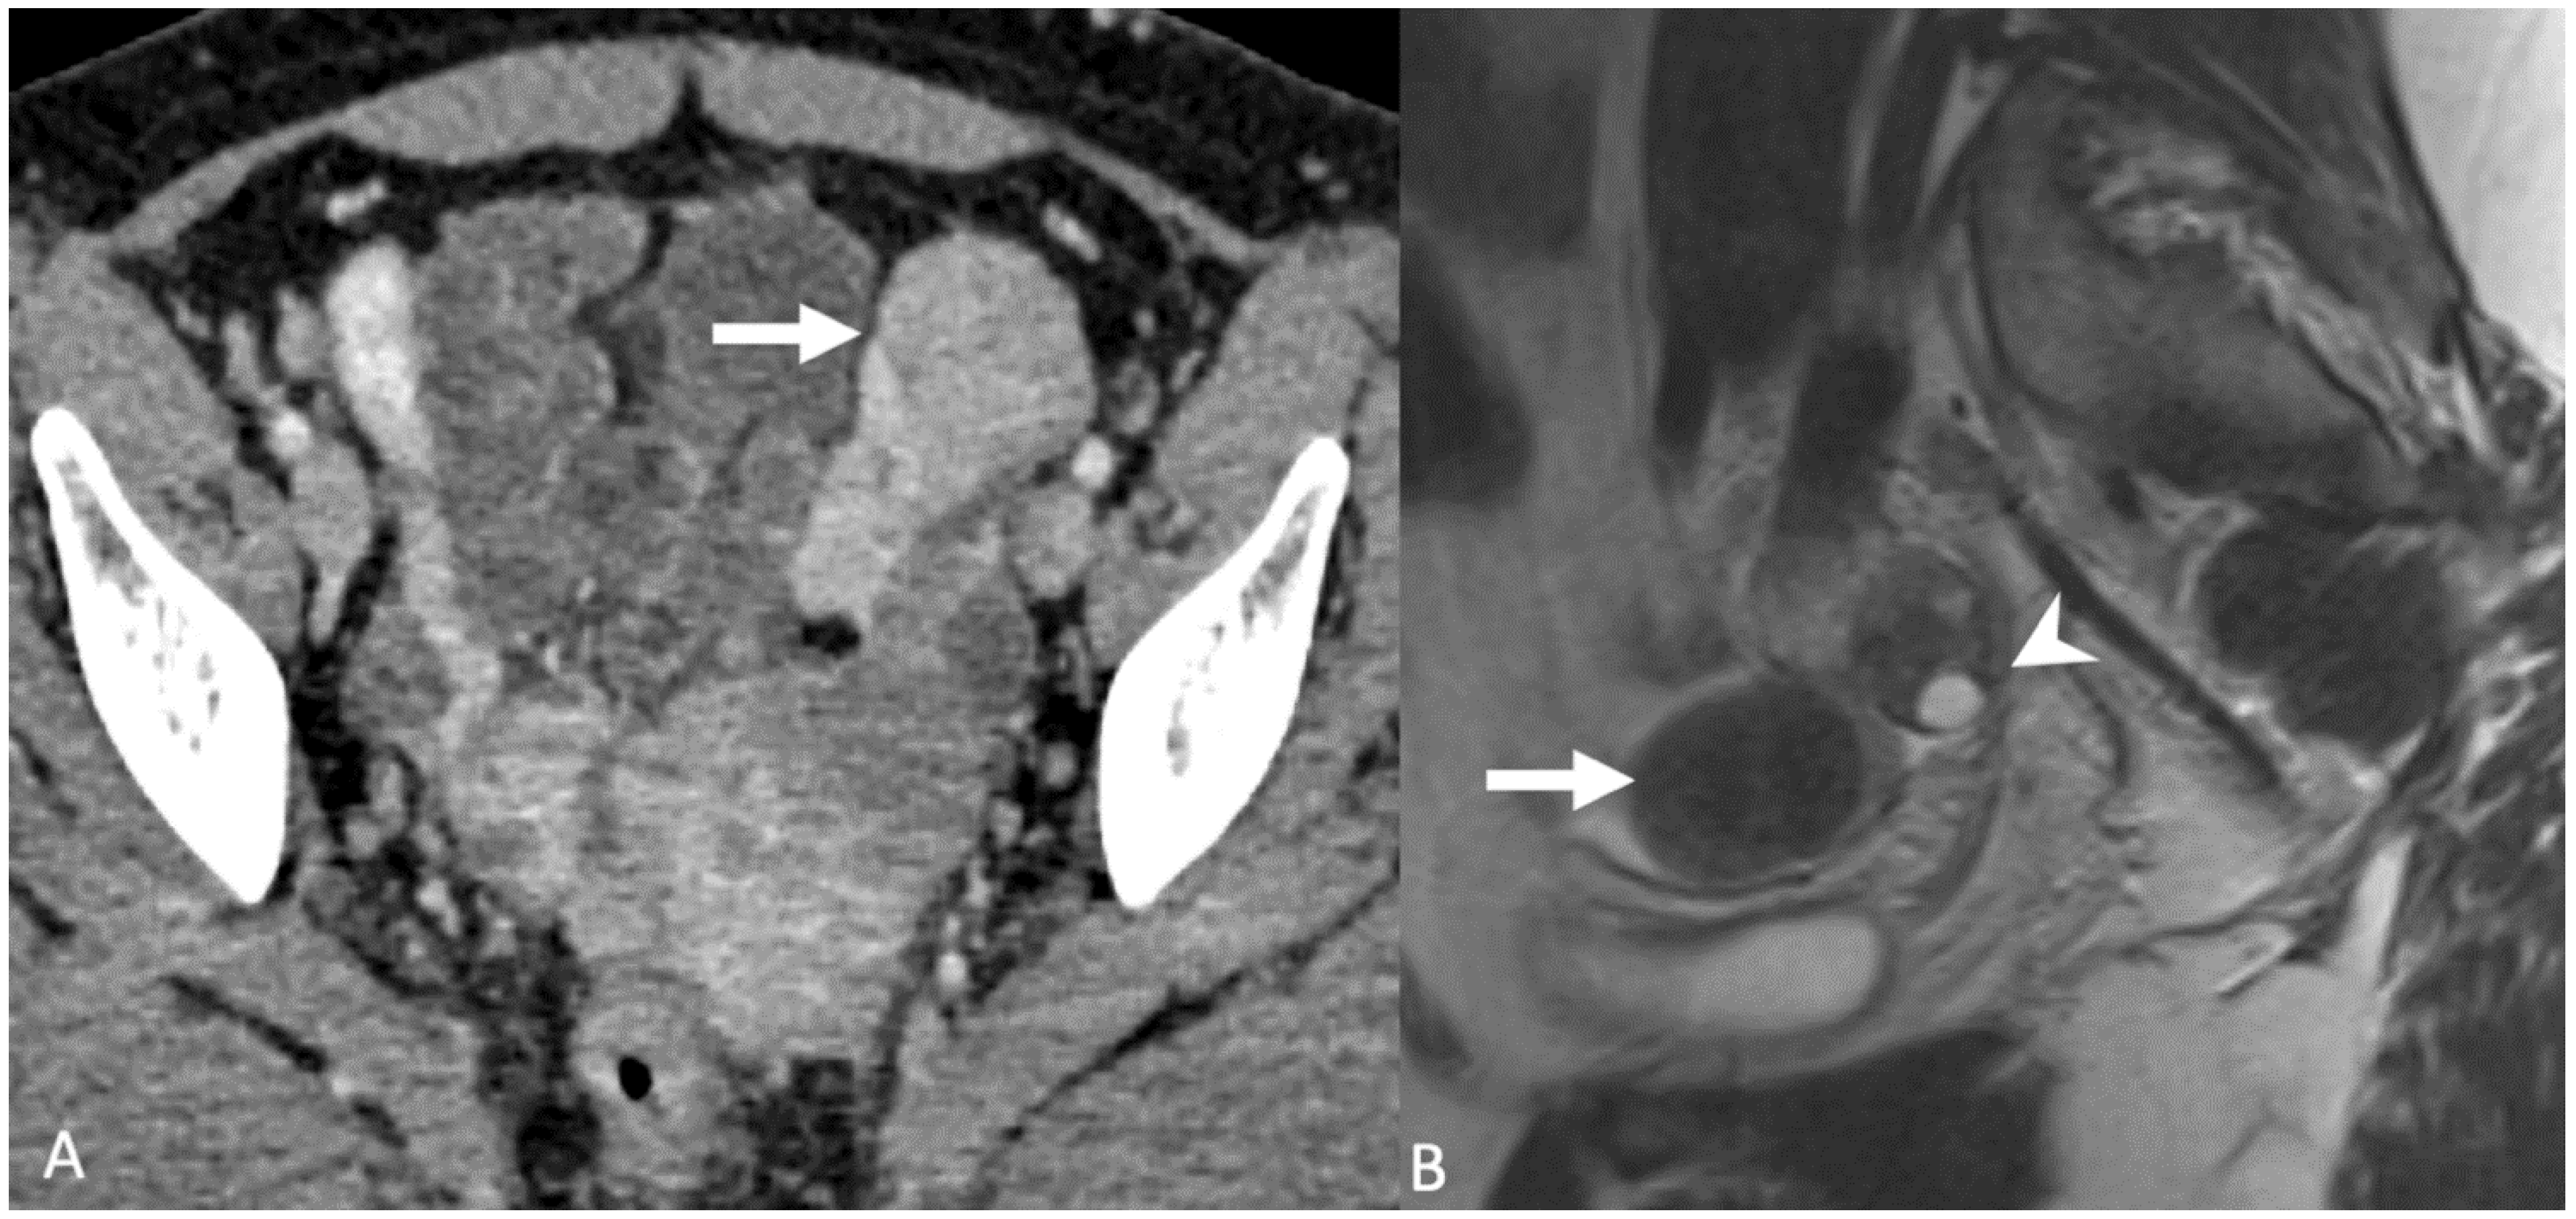

5.3. Peritoneal Disease

5.3.1. Disseminated Peritoneal Leiomyomatosis